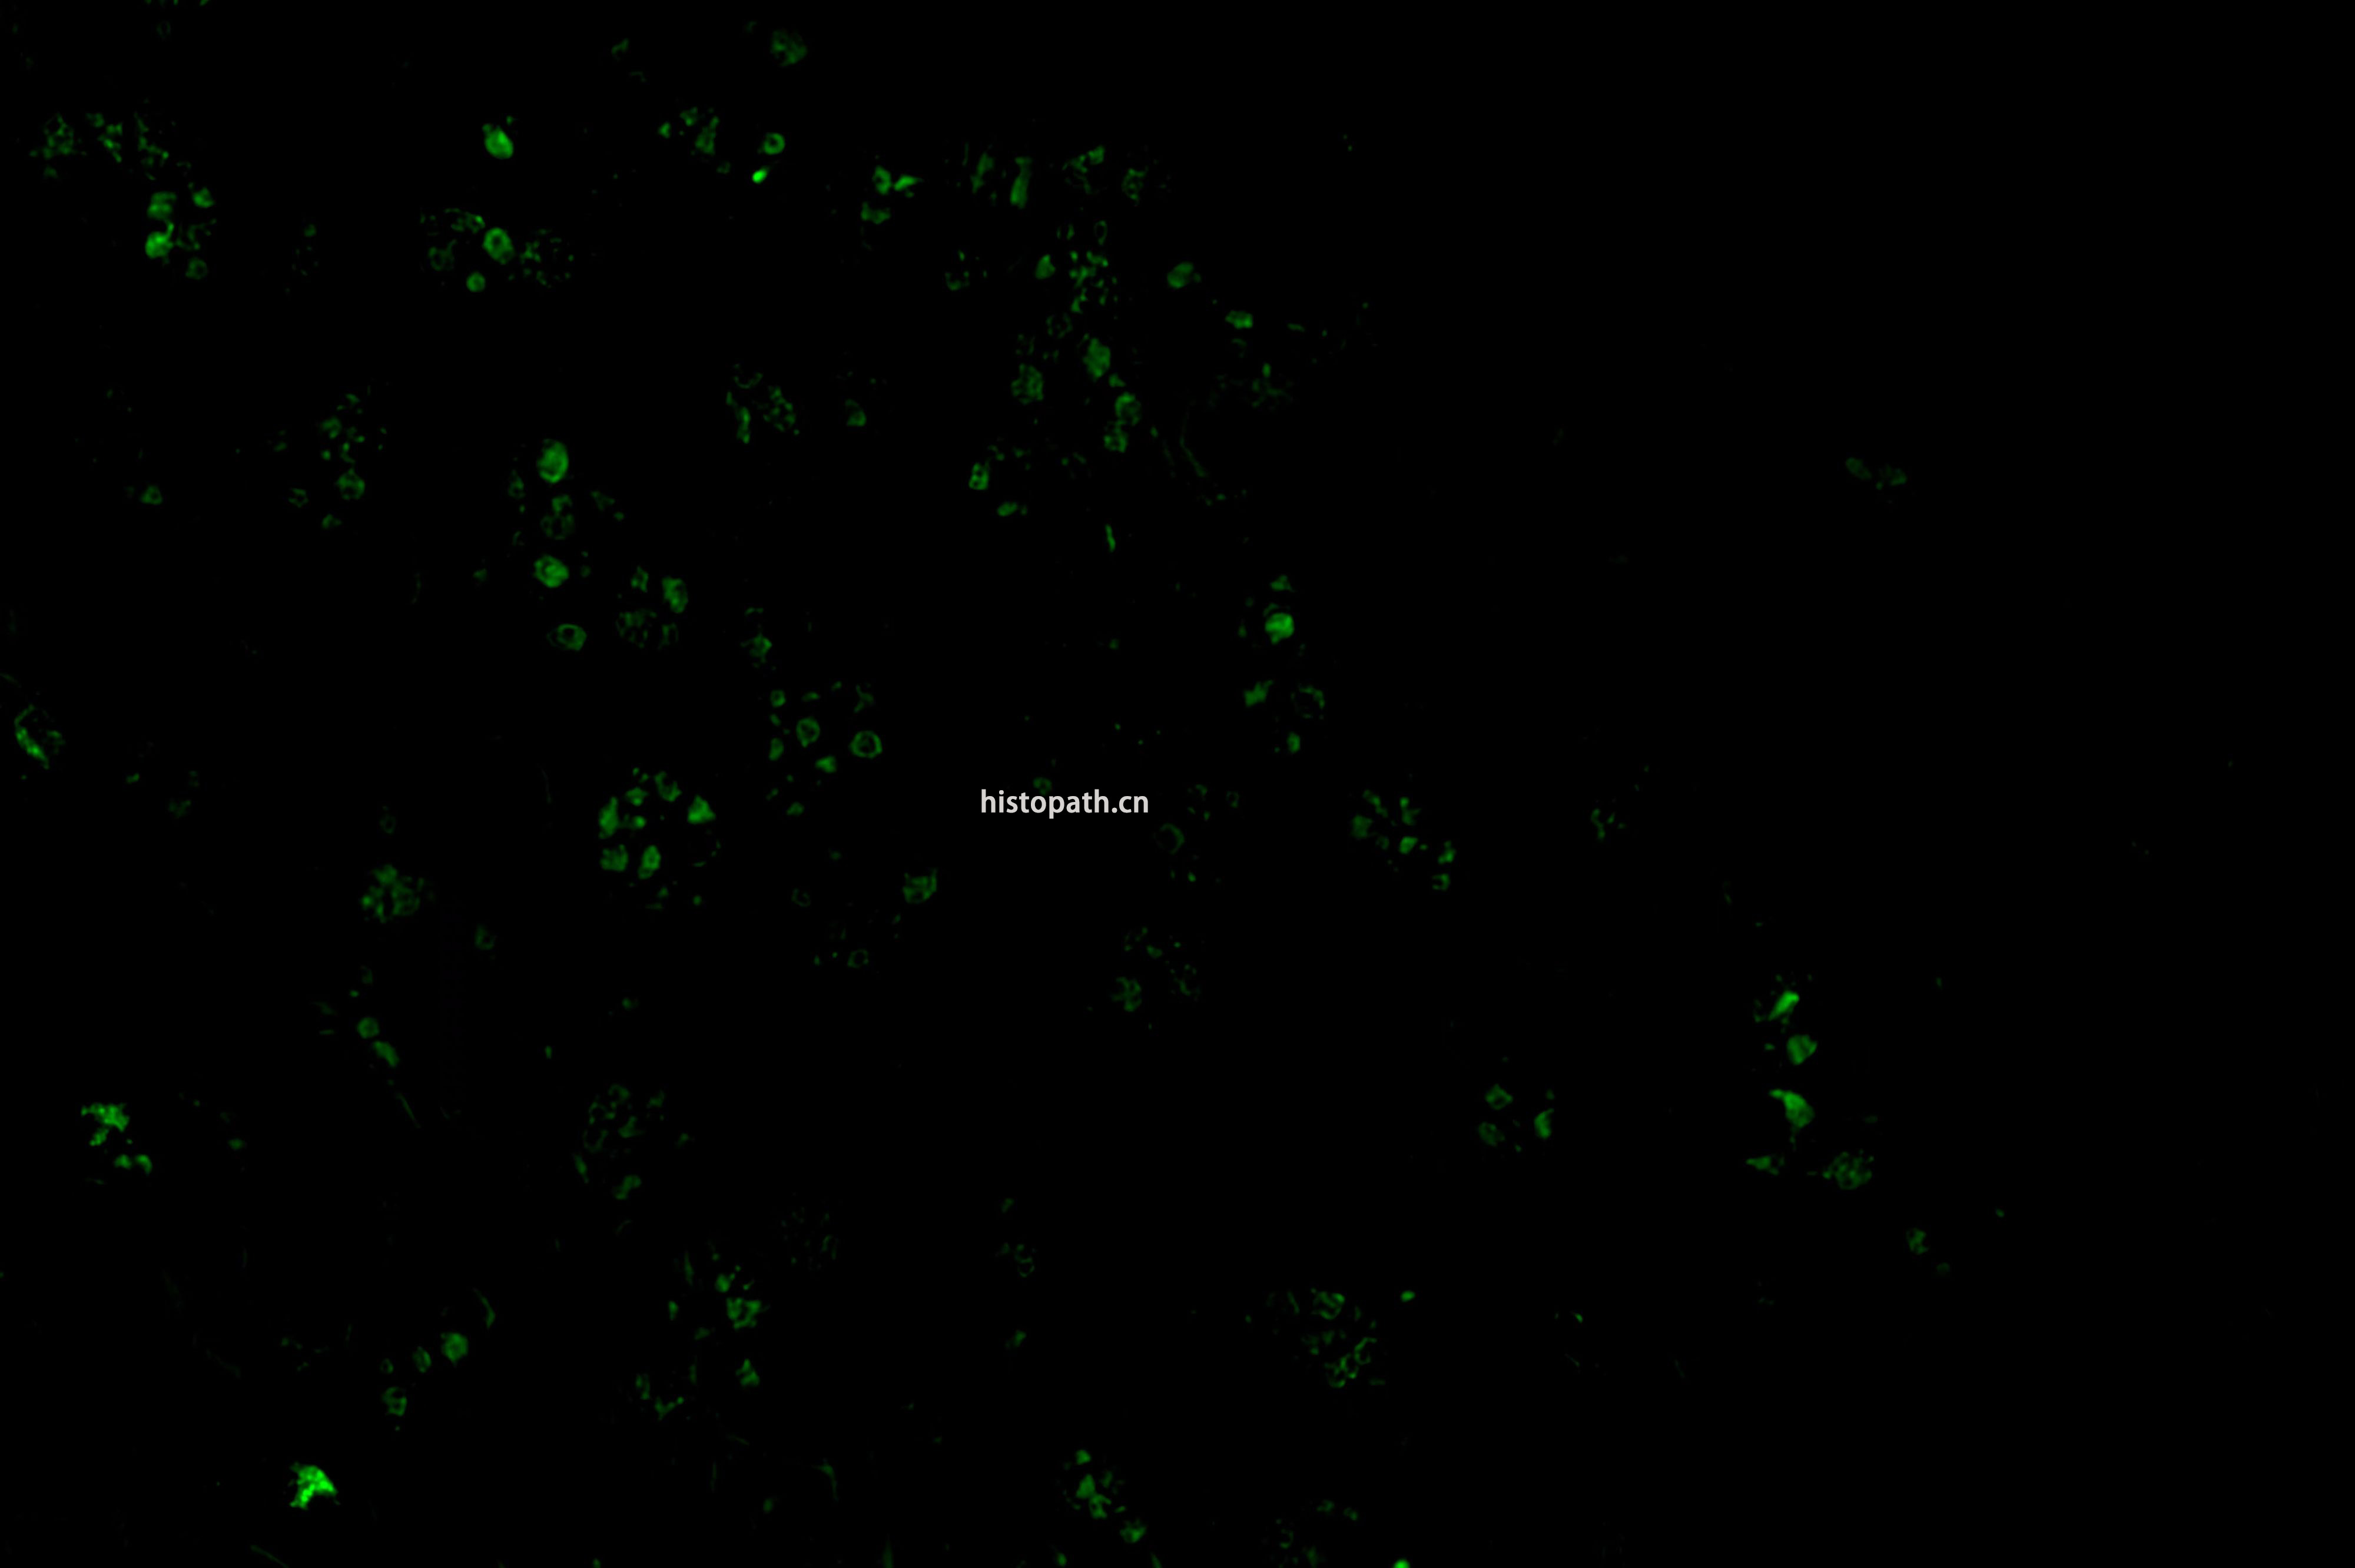

TUNEL染色荧光法

TUNEL检测原理:

细胞在发生凋亡时,会激活一些DNA内切酶,这些内切酶会切断核小体间的基因组DNA。细胞凋亡时抽提DNA进行电泳检测,可以发现180-200bp的DNA  ladder。基因组DN A断裂时,暴露的3'-OH可以在末端脱氧核苷酸转移酶(Terminal Deoxynucleotidyl TransferaseTT)的催化下加上绿色荧光探针荧光素(FITC)标记的dUTP(fluorescein-dUTP),从而可以通过荧光显微镜或流式细胞仪进行检测,这就是TUNEL(T dT-mediated dUTP Nick-End Labeling)法检测细胞凋亡的原理。